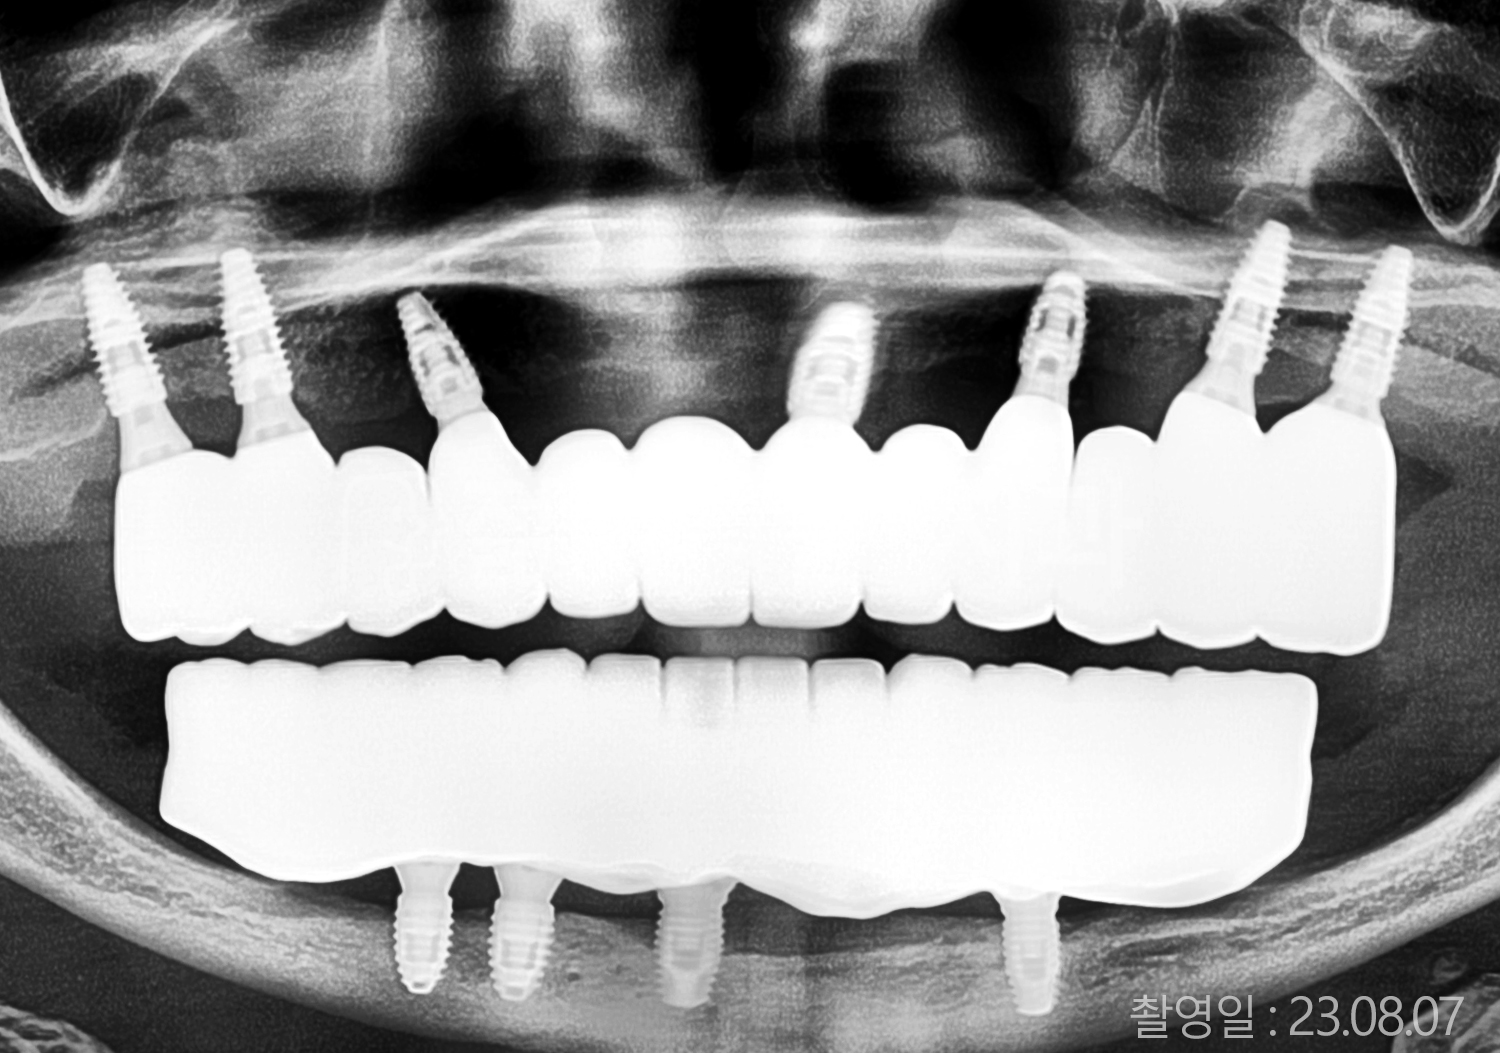

• 50대 고혈압, 당뇨, 고지혈증 전체치아 10개 이상 임플란트

• 50대 고혈압, 당뇨 전체치아 10개 이상 임플란트